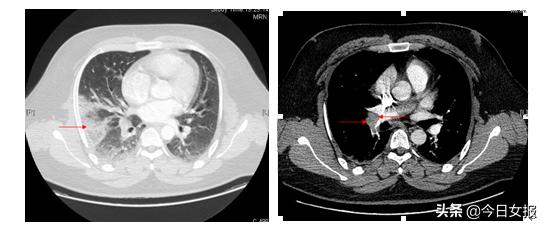

在呼吸与危重症医学科重症监护病房,梁伟军副主任医师仔细查问了小威的病史和作息情况,通过“通宵达旦玩游戏”“每日的运动步数在500以内”“出现胸痛咯血及呼吸困难的症状”这些信息,判断小威可能患上了呼吸科致死性疾病—急性肺栓塞,于是为其进一步完善肺动脉CT血管造影(CTPA),根据检查结果最终确诊急性肺栓塞,立刻进行对症治疗,由于救治及时,小威症状很快得到改善。